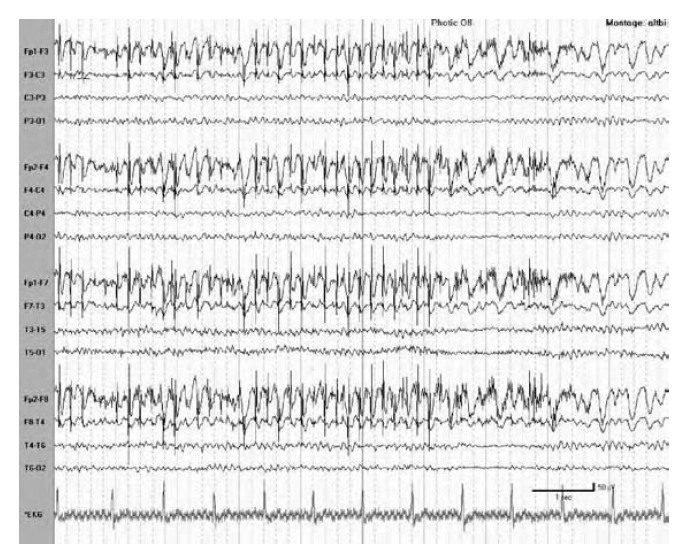

THIS IS AN ARTIFACT. BUT WHAT ABNORMALITY DOES IT MIMIC?

Eye movement monitors confirming a vertical eye flutter artifact with infraorbital electrodes (EOGs) during intermittent photic stimulation (IPS) to differentiate an artifact from frontal intermittent rhythmic delta activity

(FIRDA).